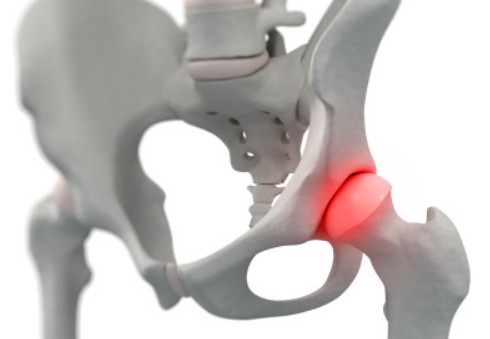

고관절 통증 원인 ⑦ 고관절의 무혈성 괴사

무혈관성 괴사는 혈액 순환에 문제가 생겨서 뼈가 손상되는 질병으로, 대퇴골두 무혈관성 괴사는 허벅지 뼈인 대퇴골의 머리 부분에 혈액 공급이 원활하지 못해 일어납니다. 이 질병은 주로 30~50대에서 발생하며, 남성에 더 많이 나타납니다. 60% 이상의 환자가 양쪽 고관절의 대퇴골두 무혈관성 괴사를 겪습니다. 이 질병을 일으키는 위험 인자로는 음주, 부신피질 호르몬 투여, 고관절 부위 외상, 잠수병, 통풍, 혈청지질 이상, 만성 신질환, 만성 췌장염 등이 있습니다. 특히 음주와 부신피질 호르몬제가 전체 원인의 90% 정도를 차지합니다.